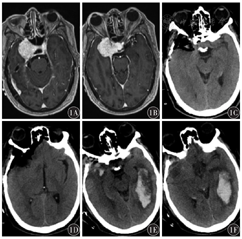

常规组术后颅内再出血32例(30.5%),预防组7例(12.5%),预防组再出血发生率明显低于常规组,差异有统计学意义(P<0.05)。常规组再出血部位幕上28例,幕下4例;术区附近出血19例,硬膜外出血5例,硬膜下出血3例,蛛网膜下腔出血3例,远隔部位出血2例。根据多田公式的计算,患者出血量10~20 ml 17例,21~30 ml 7例,31~40 ml 4例,41~60 ml 4例。常规组中1例右侧鞍旁脑膜瘤患者,术后当天复查CT颅内未见再出血,由于术中释放脑脊液速度过快,颅内压波动剧烈,术后次日CT示术区对侧颞枕叶新发脑内血肿(图1)。预防组再出血部位幕上6例,幕下1例。出血量在10~20 ml 5例,21~30 ml 2例。